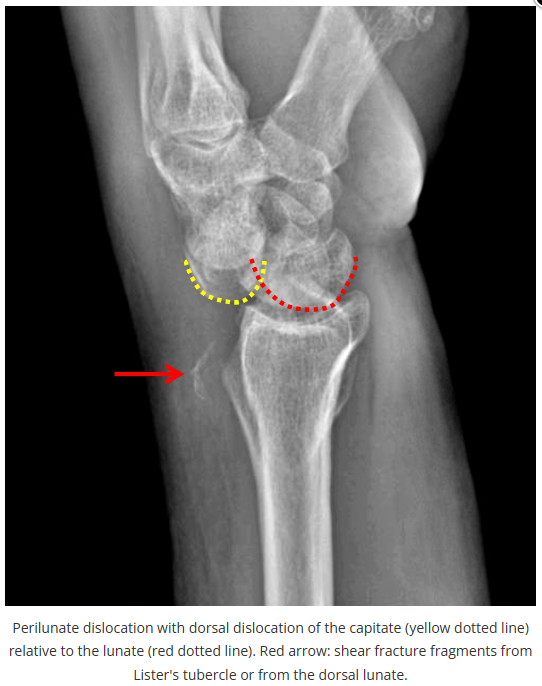

这些腕与手的骨折X线片如果没有标注箭头,你还能识别出来吗?

X线读片是骨科医生的基本功。

今天是腕部与手的X线片。所有X线片都

带有标注和说明

,可以选择长按图片,

自动翻译相关说明

。